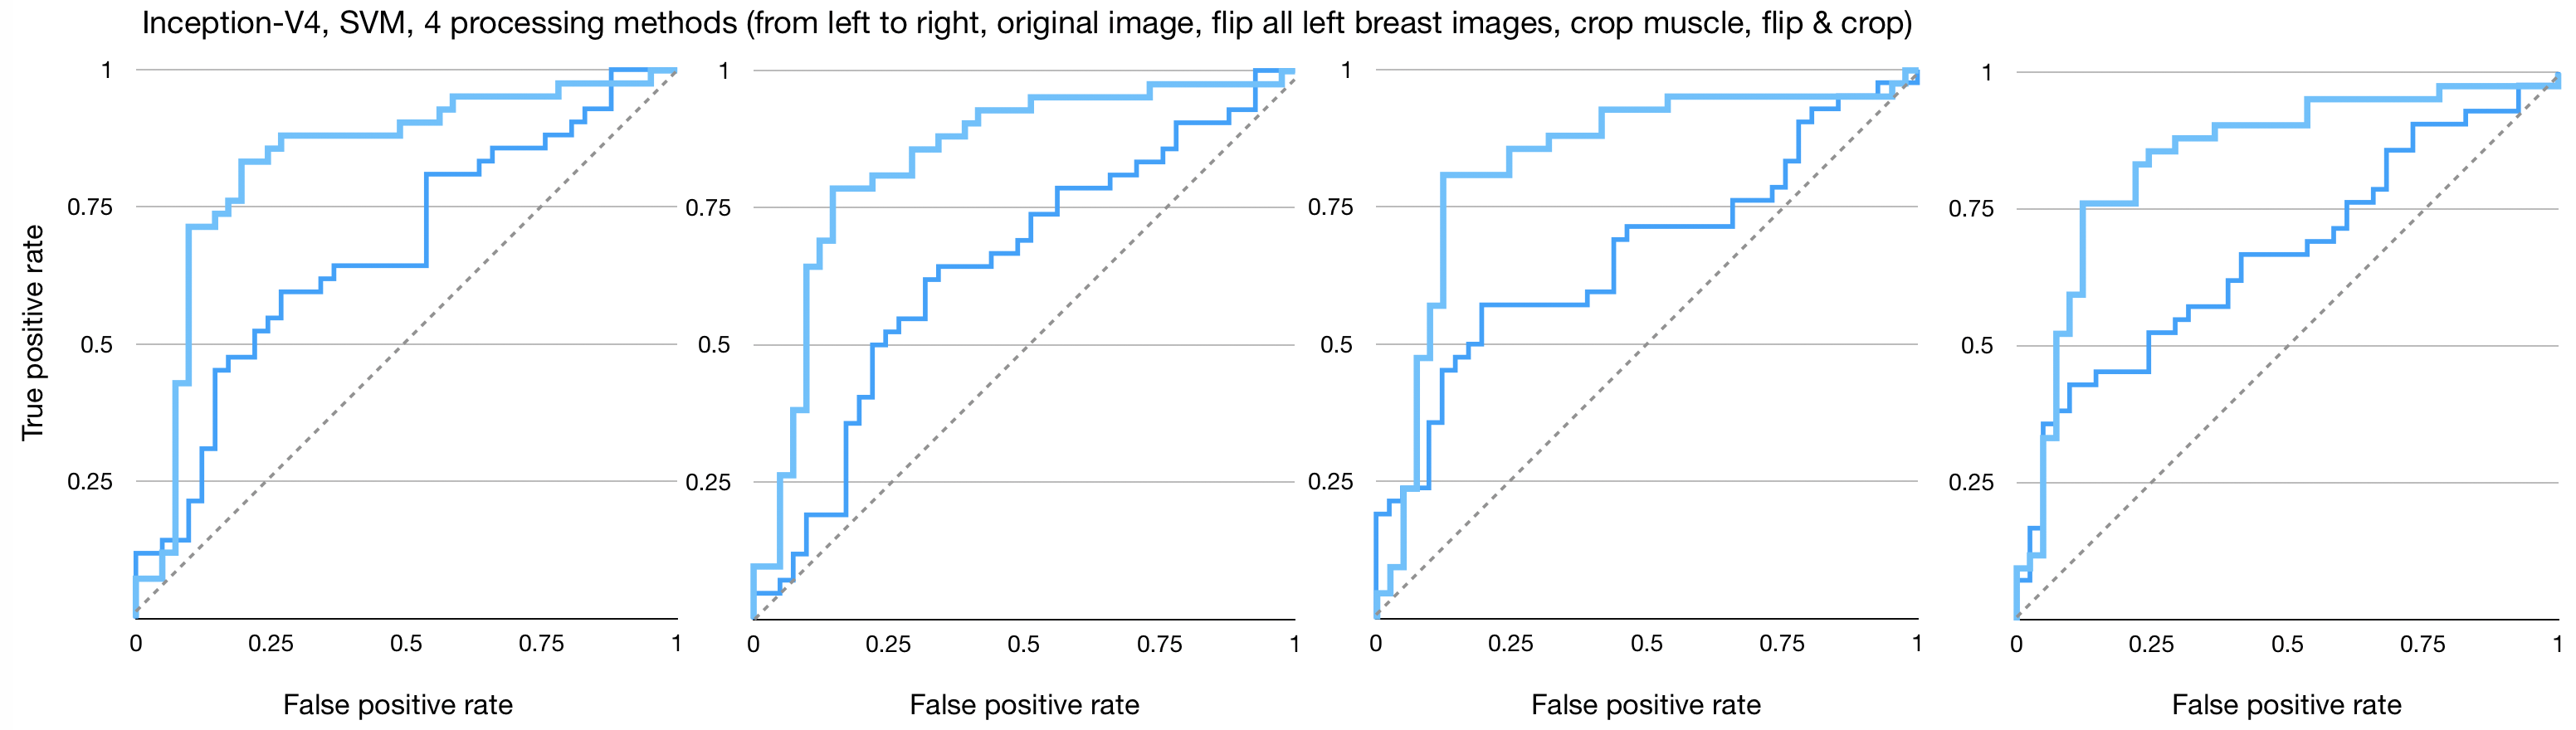

Figures 4, 5, and 6 show the imaging for which both humans and CNNs make mistakes, model introduced errors, and model corrected human errors. Figure 7 shows the receiver operating characteristic curve (ROC curve) for each of the 16 end-to-end models between the CNNs and radiologist gist plus CNNs. Tables 1 and 2 show the AUC data and differences used in the main text from the 16 conditions we have tested. Although the present work provides knowledge about adding radiologists’ data into CNN, it does not allow for training on new data, thus restricting our application domain to a small range of in-house data.